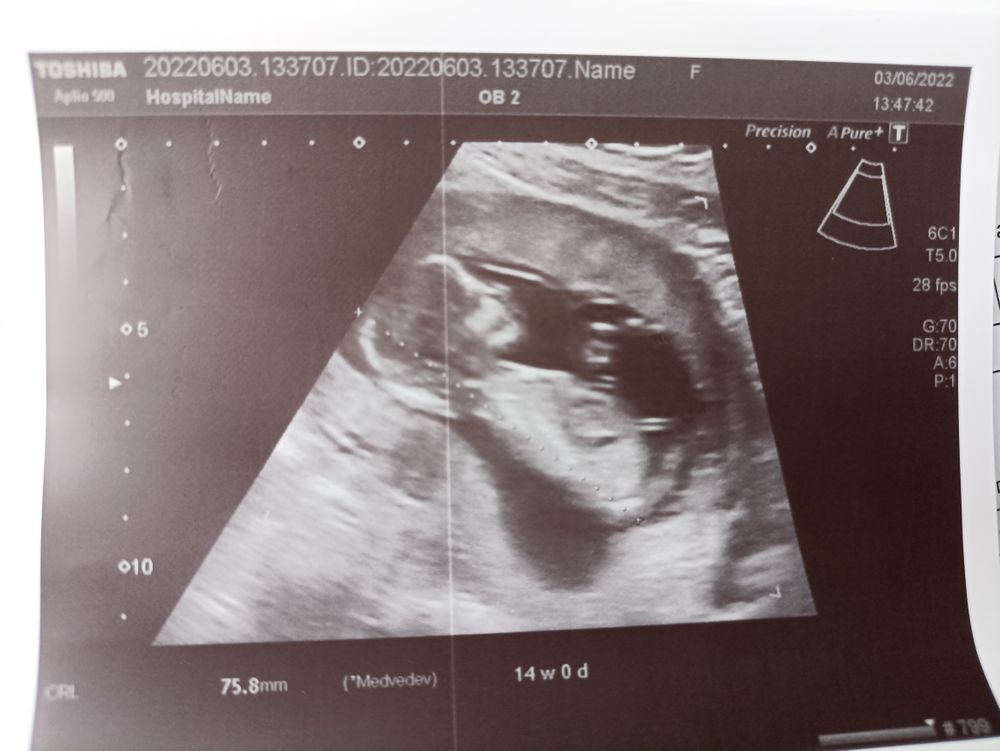

Мои дорогие просили фото в полный рост! Воть жду ваших вариантов кто это пишите в комментариях